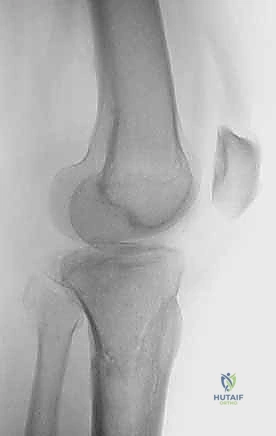

2. التصوير الإشعاعي (X-rays)

الخطوة الأولى هي التقاط صور أشعة سينية من عدة زوايا (أمامية خلفية، وجانبية). تعطي الأشعة السينية فكرة عامة عن وجود الكسر وموقعه، لكنها غير كافية لتقييم الكسور ثنائية اللقمة المعقدة.

3. الأشعة المقطعية المحوسبة (CT Scan) - المعيار الذهبي

لا يمكن إجراء جراحة لكسر ثنائي اللقمة دون إجراء أشعة مقطعية (يفضل مع إعادة بناء ثلاثية الأبعاد 3D).

* توفر الأشعة المقطعية خريطة دقيقة لكل شظية عظمية.

* تحدد مقدار الانخساف في السطح المفصلي بالمليمتر.

* تكشف الشظايا المخفية، خاصة في الجزء الخلفي من الركبة (Posterior Coronally oriented fragments) والتي تتطلب خطة جراحية خاصة لتثبيتها.